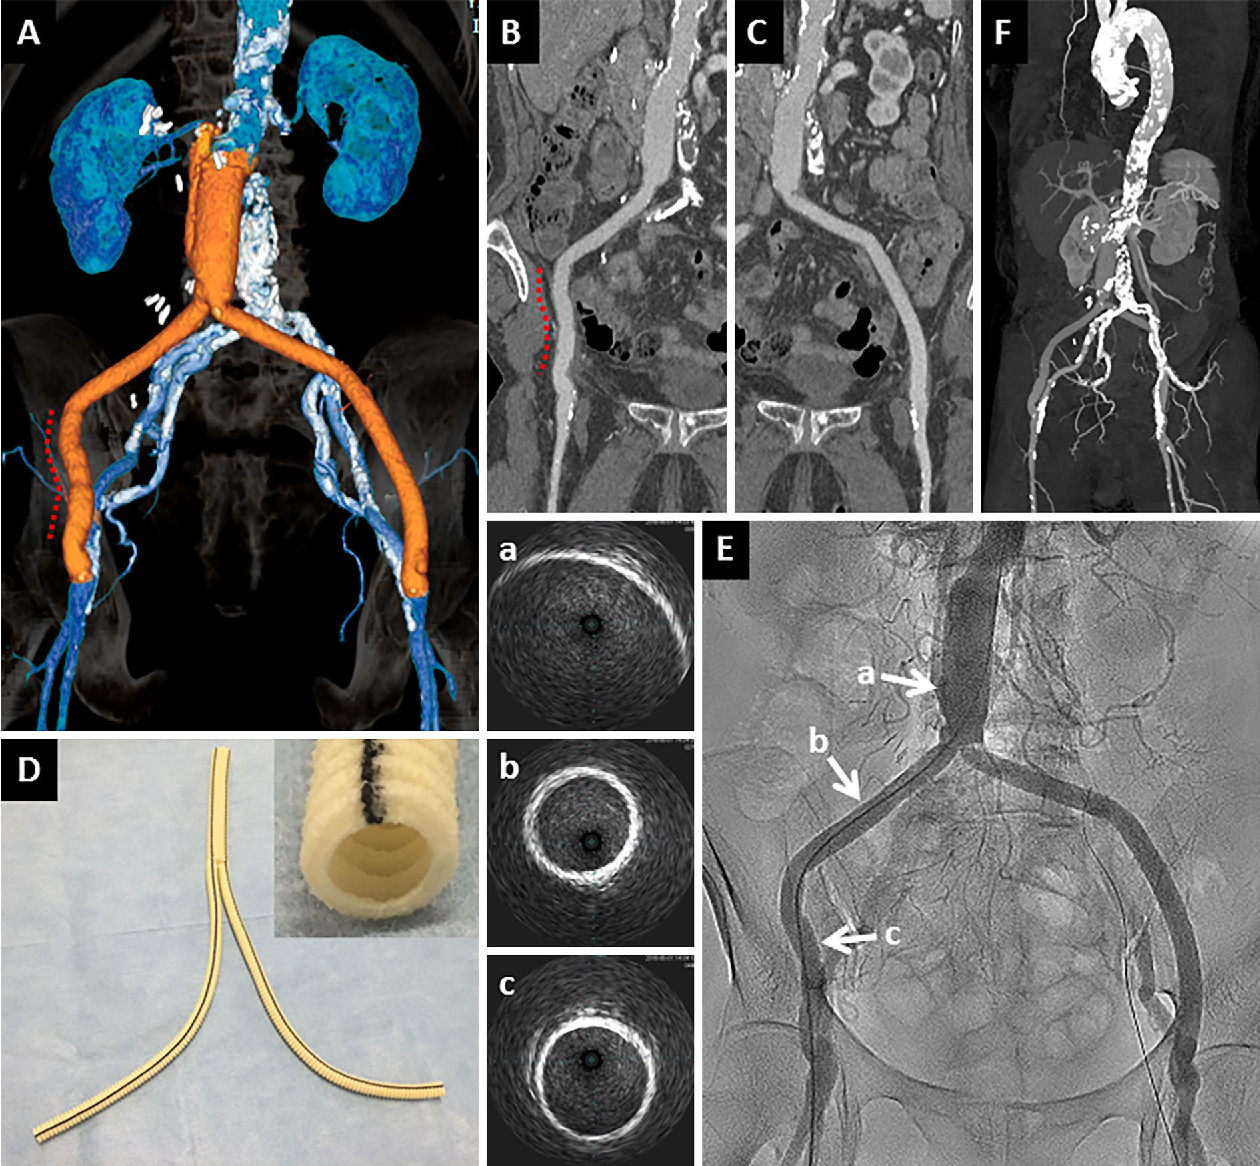

Explore clear Mandibular Tori pictures to understand these common bony growths on the lower jaw. Learn about the causes, symptoms, and potential treatment options for oral exostosis. See what mandibular tori look like in this visual guide to help identify your own symptoms and determine when to consult a dentist for professional oral health advice.